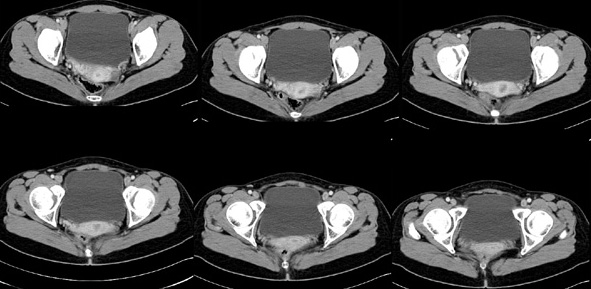

女性,28岁,停经3月,腹部膨隆1月,产前检查发现腹部占位

{肿块中心ct值27hu,增强后,动脉期、门脉期均无明显强化)

患者手术病理:腹腔囊性淋巴管瘤,象这样充满整个腹腔的的确很少见